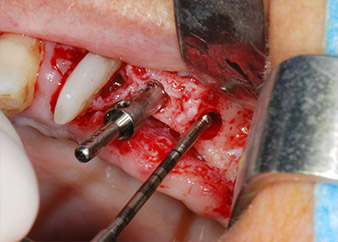

Vor der Insertion der Implantate wurde infiziertes Weichgewebe im Implantationsbereich und um das Abutment mit einem Instrument entfernt, das laut Hersteller primär zur Knochenbearbeitung und zum Sammeln von Knochenspänen vorgesehen ist (Piezomed, Einsatz B5) (Abb. 6 und 7).

Im folgenden Schritt wurde das jeweilige Implantatbett an den Positionen 25 und 26 mit rotierenden Instrumenten in einem Winkelstück mit einem Übersetzungsverhältnis von 20:1 (WS-75 L G, W&H) und einem vor Kurzem aktualisierten leistungsstarken Implantatmotor präpariert (Implantmed, W&H) (Abb. 8 und 19).

Die Abschlusspräparation am Sinus erfolgte wieder mit einem piezochirurgischen Instrument.

Vor der Insertion der Implantate und nach Überprüfung der intakten Schneiderschen Membran (Abb.9) wurde der interne Sinusboden an beiden Implantatpositionen mittels eines xenogenen Knochenersatzmaterials (Abb. 10) augmentiert.

Dann wurden die Implantate (Restore, Keystone Dental) mit dem Implantatmotor eingesetzt (Abb. 11 und 12).